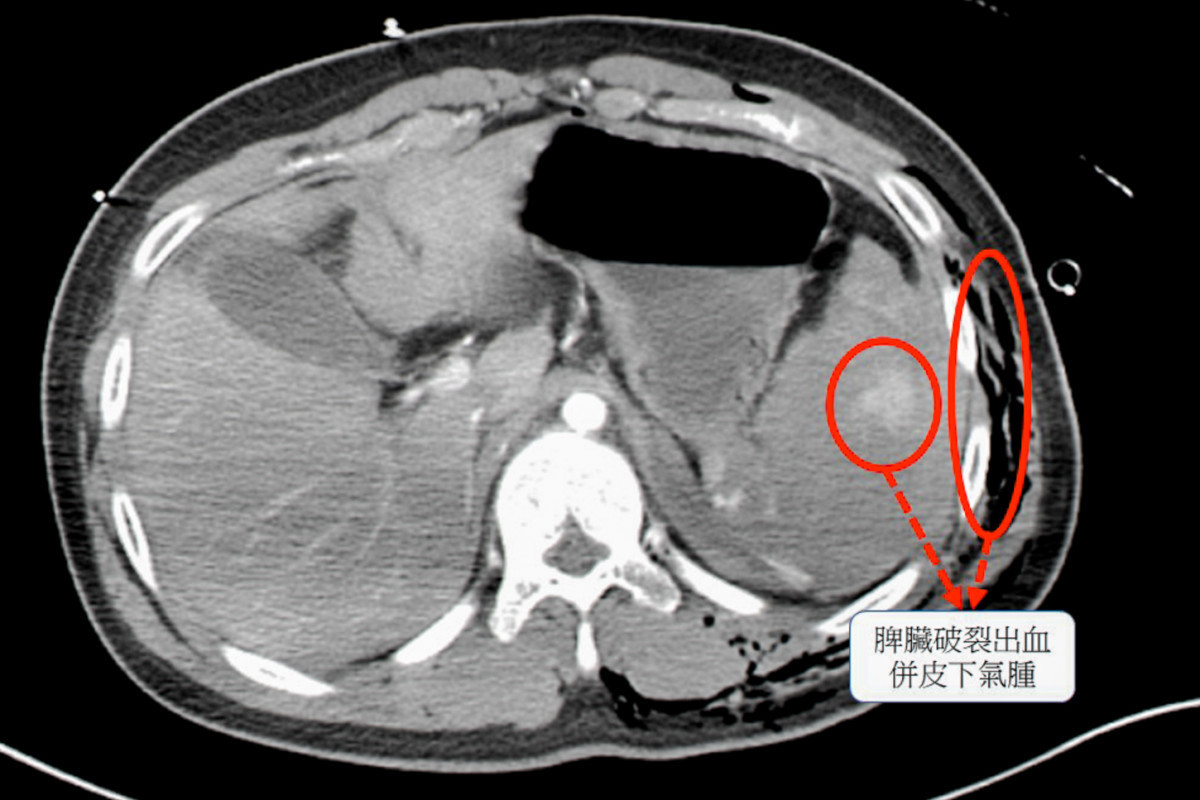

經過電腦斷層檢查,確認患者的脾臟已完全碎裂,是體內大出血的主因 ,同時合併胸腔積血、積氣,以及多處骨折與血管撕裂傷 。

電腦斷層檢查顯示,患者脾臟已嚴重碎裂,為大量出血的主要來源,並合併胸腔積血積氣、多處骨折及血管撕裂傷。外科團隊第一時間完成脾臟切除手術控制出血,隨後骨科與整形外科醫師接手進行骨折固定與血管修補,成功穩定患者生命跡象。

19歲男性患者因自摔導致脾臟破裂,接受緊急手術,經多科團隊緊急手術止血與修補,術後因急性肺損傷啟用葉克膜支援心肺功能,成功搶回生命契機(示意圖)。